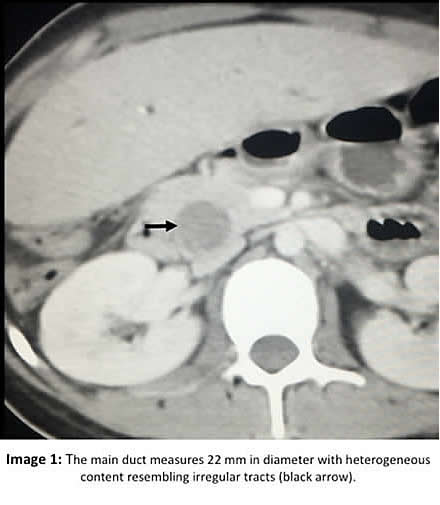

Epidemiology: Patient was born and lives in Lima. Her only travel was a single trip to Huaraz, state of Ancash in the Peruvian Andes, years ago. Has contact with dogs and cats. Denies living near a slaughterhouse. No known TB exposure. No ingestion of aquatic plants. No weight loss, no IV drug use, no alcoholism, or new sexual partners. Physical Examination: BP 82/36, HR: 124, RR: 24, Temperature 38C, Sat02 96% at room air. Patient appeared acutely ill with moderate respiratory distress No edema, no cyanosis, Skin: Jaundice 3+. Abdomen: Distended, bowel sounds present, diffuse pain on deep palpation, no peritoneal signs. Enlarged liver (5 cm below right margin). No splenomegaly or lymphadenopathy. Glasgow coma scale 15. Laboratory: Hb 10.2. Hct 31. WBC 16,600 (3 band, 82 neutrophils, 1 eosinophils, 8 monos, 5 lymps). Glucose 96. Urea 22.4. Creatinine 0.3. Bilirubin 18.5 with 16.7 direct. AST 76 ALT 76, alkaline phosphatase 387 (<150 mg/dl). HIV Negative. HBsAg Negative. HAV IgM Negative. Abdominal CT (Image 1) is shown.

![]() Discussion: At surgery, the dilated main bile duct was opened and white membranes were extracted with approximately 300mL of purulent biliary secretion. The cyst in the main bile duct seemed to extend into the liver parenchyma. The abdominal CT-scan was read as showing an enlarged liver with dilatation of intrabiliary ducts and signs suggestive of cholangitis. The main duct measures 22 mm in diameter with dense heterogeneous content, resembling linear and irregular tracts (Image 1 arrow). There is a liver cyst of 11.5 cm in vertical diameter by 4.5 cm in transverse diameter; this cyst has heterogeneous content suggestive of detached membranes that are also seen in the dilated main duct, representing a communication between both (Image 2 arrow). Hydatid cyst rupture is classified into three types: a) contained rupture, when the endocyst (acellular multilaminated membrane and nucleated internal germinal membrane) ruptures but the content is confined within the pericyst (compressed host organ parenchyma), b) communicating rupture, when cyst content escapes usually into the biliary tract because the pericyst incorporates biliary branches as it expands, and c) direct rupture when both endocyst and pericyst tear and the full content splits into the pleural or abdominal cavity (AJR 1988;150:1051-3). When the cyst communicates with the biliary tract it may involve the common hepatic duct, lobar branches or small intrahepatic branches, the latter are most commonly involved. Small communications between liver cysts and the biliary tree seem to be common (40-90%) and are usually asymptomatic, but large tears are less frequent (5-10% of these) causing biliary tree obstruction and potentially serious complications such as cholangitis, hepatic abscesses, acute cholecystitis, acute pancreatitis and even biliary cirrhosis (Br J Surg 1971;58:228-32; AJR 1982;139:699-702). CT can help identifying the communication between the liver cyst and the biliary tract by showing the defect or discontinuation of the cyst or indirectly by showing linear and irregular tracts inside the biliary tract as in this case (Image 1). Multidetector CT enhances the view of the common bile duct and may be used as an adjunct diagnostic technique in cases of suspected major tears into the biliary tract (Abdom Imaging 2011;36:433-7). ERCP may be used to remove the contents of the cyst, but usually surgical exploration is needed. When a hydatid cyst becomes infected, the bacteria digest all the cyst contents and the membranes, so that in the pathology examination only the remaining hooklets can be found, the membranes and protoscolices cannot be found. In this case, the infection had not yet digested the complete membranes, that is why they were still identifiable but with degeneration (Image 3 showing internal germinal and external acellular multilamellated membrane). The remaining cyst cavity contents are probably dead, but just in case we decided to give albendazole for three months after surgery. Human hydatid disease secondary to Echinococcus granulosus is caused by the larval form of this dog tapeworm. Humans ingest the tapeworm eggs in environments contaminated by canine feces and become accidental intermediate hosts. Sheep are the normal intermediate hosts. In general, disease is diagnosed in adulthood as larval cysts expand slowly over years or decades, becoming symptomatic as they impinge on other structures by virtue of their size. The cysts contain hundreds of viable protoscolices capable of becoming adult tapeworms upon ingestion by a definitive host such as the dog. The cyst wall is composed of a 1 mm thick acellular multilaminated membrane, followed by the nucleated internal germinal membrane that is about 0.1 mm thick. The internal germinal membrane lining the cyst produces new protoscolices on an ongoing basis. Each protoscolex is capable of becoming a new daughter cyst should the original cyst rupture or be ruptured. Cystic hydatid disease due to E. granulosus is common in sheep and cattle raising areas worldwide. Most primary infections involve a single cyst. In adults, 65% of solitary cysts are found in liver, 25% in lung and the rest in a wide variety of other organs including kidney, spleen, heart, bone and brain. In patients with a pulmonary cyst, approximately 18% will also have a hepatic cyst. |